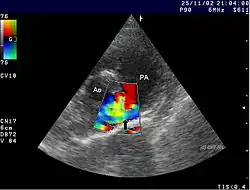

Se pueden observar cambios en radiografías del tórax. El diagnóstico se confirma con una ecocardiografía.